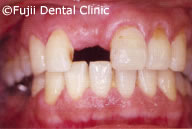

左上第二小臼歯破折による痛みがあり来院されましたが、下顎左右の大臼歯の欠損により、後方の歯が手前に傾斜、上顎大臼歯の挺出、噛み合わせのバランスが崩れてしまっていました。下顎大臼歯にインプラントを埋入することにより咬合は回復しました。挺出した上顎大臼歯は、クラウンをかぶせましたが、歯が欠損した時点ですぐ治療をしていれば、上の歯の治療は行わず最小限の治療にとどめられたでしょう。

| 補綴物(クラウン)装着時口腔内写真 |